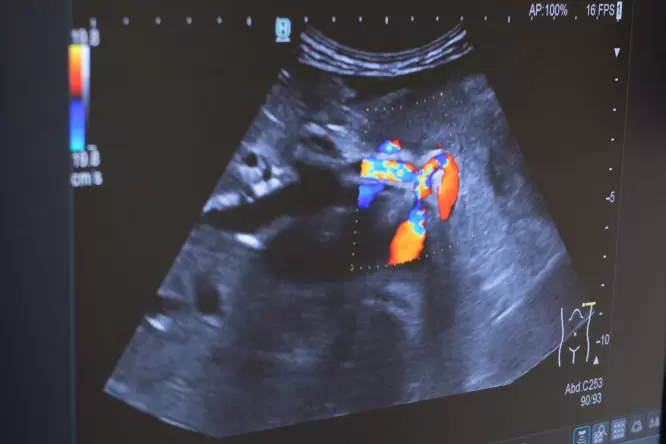

Ultraschall-Bild mit Farbdoppler, Gastroenterologie im Josephinum

Bei spezieller Fragestellung kann die zusätzliche Farbdoppleruntersuchung Aufschluss über die Durchblutung der Organe geben.